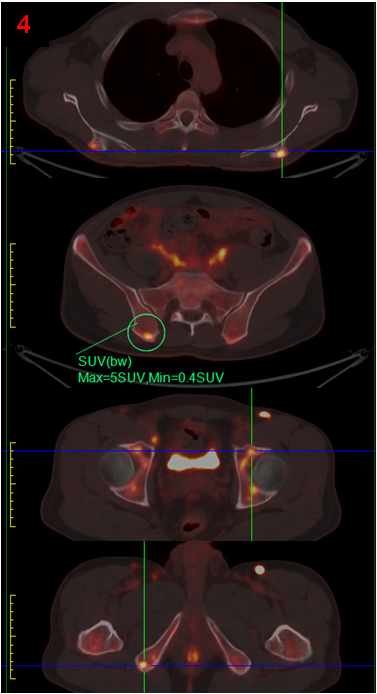

完善PET/CT檢查,示頸胸腹盆多處淋巴結或軟組織、右側腎上腺、腹膜(圖3),以及全身多處骨骼/骨髓(圖4)異常代謝,考慮淋巴瘤,建議病理檢查。

參考PET/CT結果,對代謝最高的右腹股溝區淋巴結進行了活檢,并完善了骨髓穿刺活檢病理檢查,最終證實為濾泡性淋巴瘤侵犯骨髓。

PET/CT顯示除腹膜后病變外,頸胸腹盆部存在多發高代謝淋巴結,以及多處骨骼/骨髓代謝異常,同時胰腺并未表現出異常高代謝,最后綜合考慮為淋巴瘤,并得到病理證實。

本案例充分體現了PET/CT的優勢,一是全身顯像,在圖像上“一目了然”地了解全身所有臟器組織的葡萄糖代謝情況,為診斷提供新的思路;二是代謝顯像,直接反映了組織器官的功能狀態,為診斷提供了份量極重的砝碼;尤其在淋巴瘤的診斷中,代謝程度最高的病灶意味著活躍程度最高,對其活檢結果最準確、可靠。